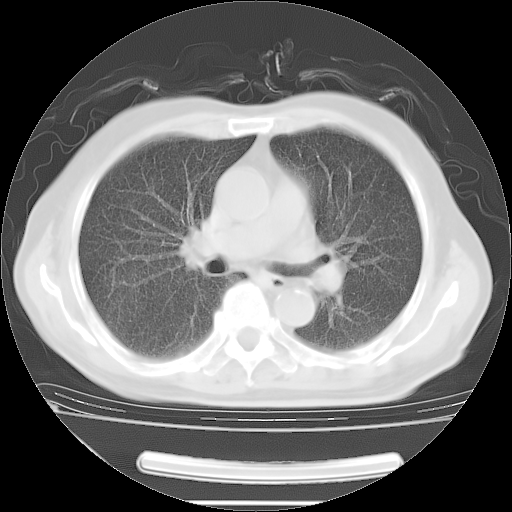

胸腹部CT,诊断意见:左上肺叶钙化灶、左侧胸膜局限性增厚并钙化、胆囊炎。描述部分肺组织呈磨玻璃样改变。